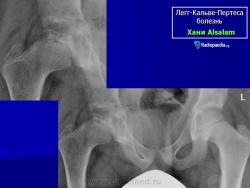

Остеохондропатия головки бедренной кости

(болезнь Легга-Кальве-Пертеса)

Рентгенологическое обследование помогает в постановке диагноза. Для сравнительного анализа производят рентгеновские снимки обоих тазобедренных суставов, а также рентгенограмму в положении Лауэнштейна. Наиболее полную информацию о локализации и распространенности патологических изменений в головке бедра дает компьютерная и ядерно-магнитно-резонансная томография тазобедренных суставов. В ранней диагностике заболевания высокоэффективно радиоизотопное исследование (сцинтиграфия).

В I стадии (асептиче­ского некроза губчатой кости эпифиза и костного мозга) изменения отсутствуют либо незначительные: в виде остеопороза костей, образующих тазобедренный сустав, извилистости и неравномерности хрящевой эпифизарной пластинки, неоднородности и пятнистости шейки бедра, некоторого расширения щели сустава.

Во II стадии (импрессионного перелома) головка бедренной кости утрачивает характерную трабекулярную структуру, шейка бедра становится более остеопоротичной. Суставная щель отчетливо расширяется по сравнению со здоровым тазобедренным суставом. Эпифиз головки уплотняется, склерозируется и деформируется (вследствие сохраняющейся нагрузки).

В III стадии (фрагментации эпифиза) суставная щель по-прежнему расширена, головка сплющена и как бы разделена на отдельные глыбки или неправильной формы мелкоочаговые фрагменты. Обычно определяется от 2 до 5 таких фрагментов, а иногда и больше. Вертлужная впадина уплощается.